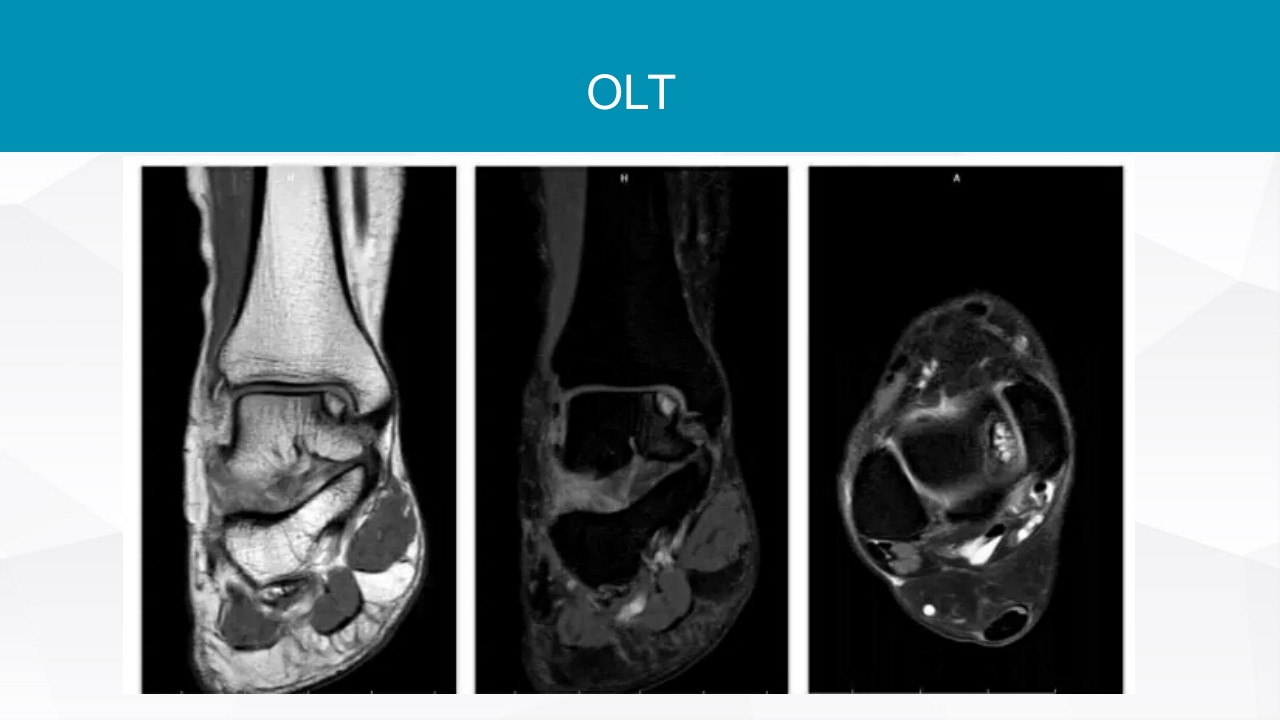

踝关节扭伤评估和治疗 LOREM IPSUM DOLOR 目CONTENTS 录 01 踝关节扭伤及损伤评估 02 踝关节扭伤的保守治疗 03 踝关节扭伤的手术治疗 踝关节扭伤 踝关节扭伤是最常见的运动损伤 85%为外踝损伤 踝关节扭伤发生机制 小腿外旋合并后足旋后 接触地面瞬间,踝关节跖 屈及内翻容易导致外踝扭伤 踝关节扭伤 踝关节外侧韧带损伤的发生率 距腓前韧带(ATFL)几乎总会损伤 跟腓韧带(CFL)受伤发生与50%~75%踝关节扭 伤 距腓后韧带(PTFL)损伤率低于10% 踝关节扭伤不能得到正确治疗 50%出现慢性踝关节不稳 15%进展为踝关节骨性关节炎 踝关节急性损伤的评估 损伤分度 I 损伤程度 ATFL损伤 II ATFL撕裂 III ATFL断裂 CFL断裂 查体发现 轻度肿胀,关节 不稳 治疗 负重功能锻...